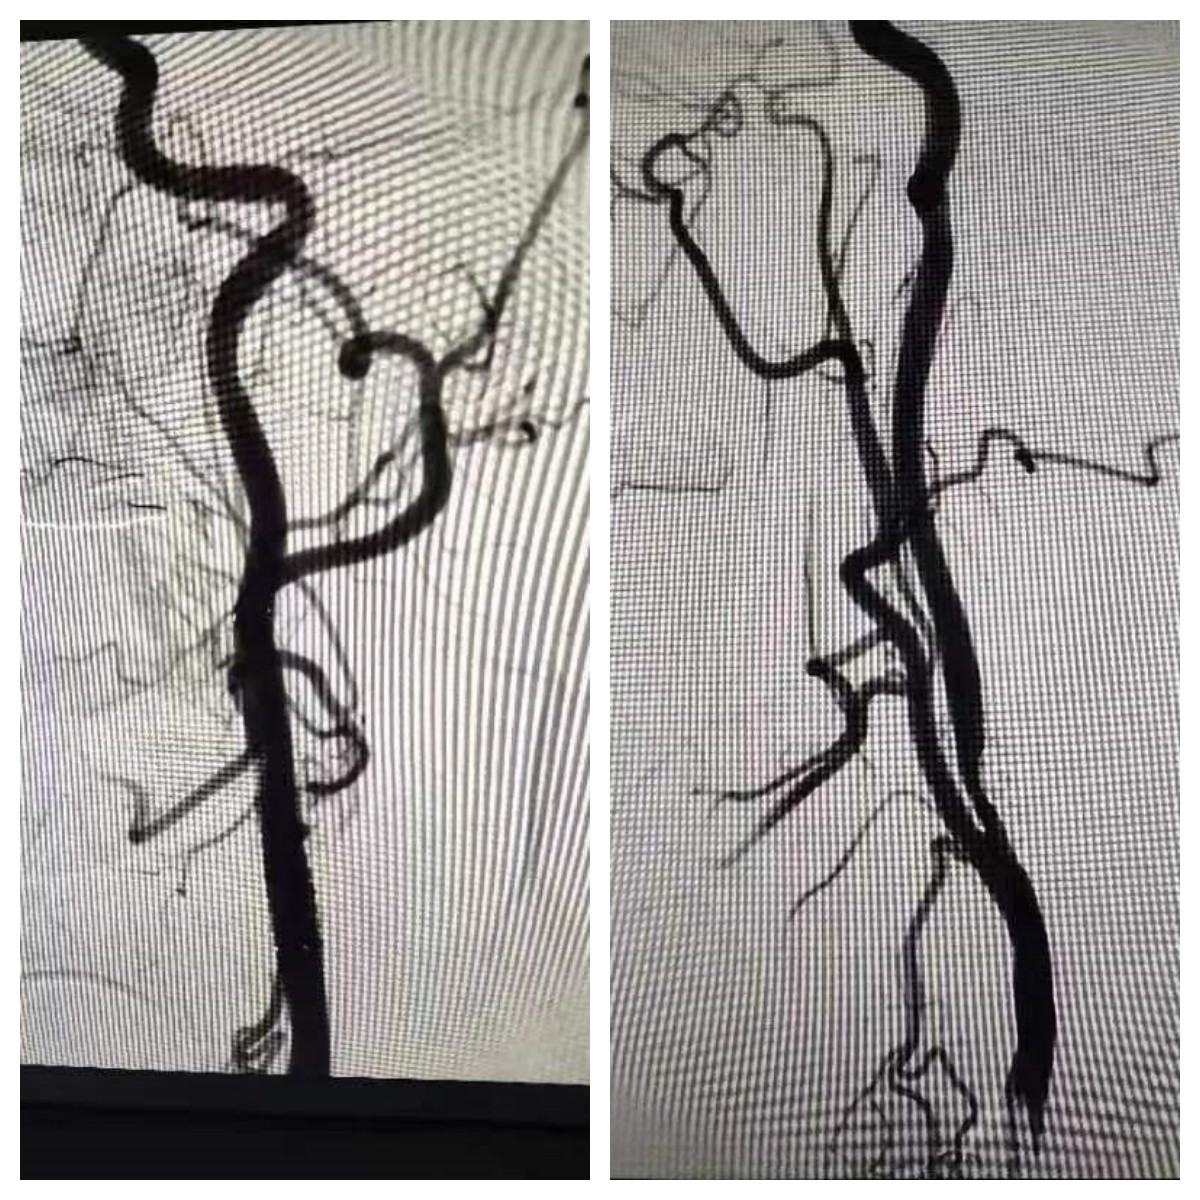

该患者于一年前无明显诱因下头晕不适,曾于宿州市医院造影显示,患者左侧颈内动脉起始部重度狭窄,在经过一年药物治疗后症状无改善,于近日就诊我院。

院神经内科团队高度重视,在与患者及家属沟通后,决定实施颈动脉支架置入术。术中,为患者进行右侧股动脉穿刺,插入一根细长的导丝沿血管进入颈动脉并将导丝放置一小型过滤网在病变部位的上方(称之为“脑保护伞”,用以拦截脱落的斑块残渣,以防止术中小的斑块随血流进入脑血管造成脑栓塞。)随后,沿着导丝放置球囊进入颈动脉狭窄部位,通过扩张球囊使狭窄部位扩张,再导入前端自膨式支架的导管放置支架。术后,患者血管血流情况得到了显著改善,头晕症状也有明显好转。

脑保护伞保护下颈内动脉支架置入术:

是在对脑血管狭窄部治疗前,将脑保护装置送到狭窄部远端,释放形成一只像雨伞一样的滤器,伞上的小孔允许血液通过,但稍大的颈动脉狭窄斑块、血栓则被挡住。颈动脉狭窄操作完成后保护伞可以像雨伞一样收拢,将收于其中的斑块、血栓带出,极大地减少了颈动脉狭窄支架置入术的并发症。